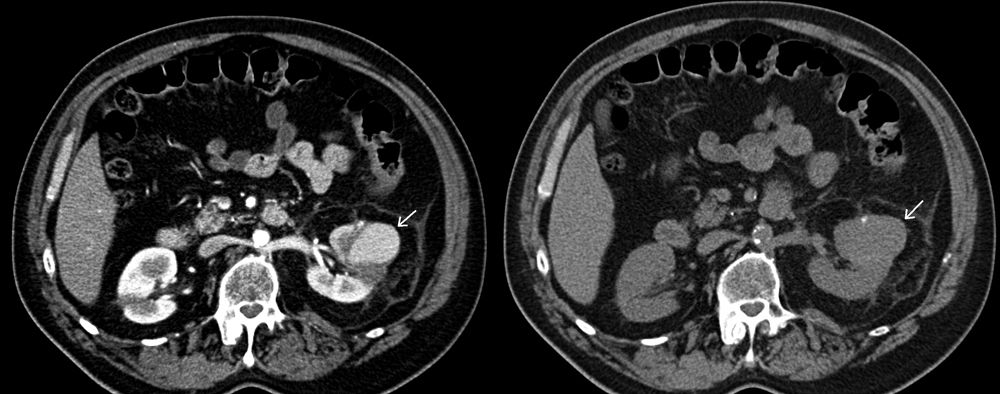

A 45-year-old female presents with gross hematuria 5 days after a laparoscopic partial nephrectomy for renal cell cancer. Images from an abdomen CT scan performed without and with IV contrast are shown, with salient abnormality indicated with an arrow. Based on the images and history, what is the diagnosis?